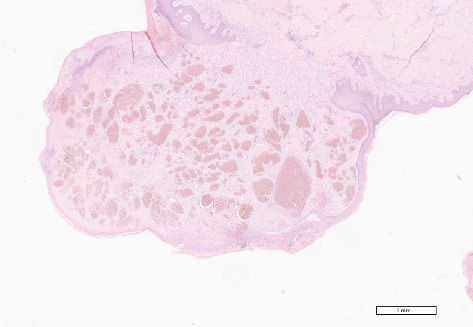

Vascular malformations are relatively common benign proliferative lesions of vascular and connective tissue origin that can present in oral regions, such as on the tongue. Etiological factors include genetic mutations or molecular changes related to syndromes, trauma, vascular wall resistance to blood flow, and may form part of other systemic diseases. Clinically, they can be extremely heterogeneous, and they can also cause important diagnostic doubts. Migratory glossitis is a very common oral condition in the general population, linked to immunological factors, sometimes connected with intestinal health problems. The aim of this work is to report an atypical case of ulcerated angioma on the tongue and the contemporary presence of migratory glossitis. A 54-year-old Caucasian female with a history of an intestinal cancer presented a particular exophytic lesion on the tip of the tongue where the hypothetical diagnosis of oral metastasis had been included, also for the rapid onset of the oral lesion. The dressmaker's needle trauma related to the patient's work activity could have been the triggering factor for the appearance of the neoformation. The diagnosis after histological evaluation was ulcerated capillary angioma. Due to the unusual presentation of this type of lesion, it is needed to reconsider current knowledge on the etiopathogenesis of vascular lesions and its clinical inclusion in the differential diagnosis.

Abstract Image